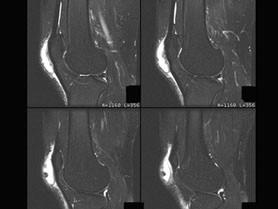

问题 男, 20岁,膝关节部前方肿痛,轻度发红、发热,结合MRI图像,最可能的诊断是 ( )

选项 A、半月板撕裂 B、髌前囊炎 C、髌骨挫伤 D、膝关节炎 E、未见异常

答案 B